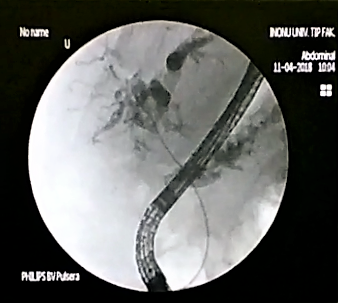

The doctors applied microwave energy to destroy tumor growth prior or post bile-duct stent installation to reestablish and maintain normal bile flow. The microwave energy is applied to the tumors in and around the duct and stent with percutaneous transhepatic cholangiography (PTC) using fluoroscope (real-time x-ray) images of liver, bile-ducts and gallbladder-ducts. A long flexible needle-catheter is inserted into the liver under fluoroscopy to locate and identify blockages using contrast dye. Once the blockage is identified, a smaller diameter catheter with microwave antenna is introduced into first catheter, the antenna is positioned along the duct and the microwave energy is applied using preset temperature and time durations. The antenna is retracted along the duct and the energy application is repeated until the desired length of the duct is treated. The doctors would remove the microwave catheter and verify bile-duct flow with fluoroscopy. The microwave energy application is controlled with direct temperature feedback from the ablation antenna during the procedure to ensure safety and efficacy.

AveCure® microwave ablation system is successfully treating tumors in bile-duct using a minimally invasive technique - the percutaneous transhepatic cholangiography (PTC) incision through the skin to access the tumor through the liver and the patient is left with a small hole in the skin, which quickly heals with almost no scar after the procedure. AveCure® system utilizes a smart antenna in either probe or catheter format and microwave energy controller to select the correct size, temperature and timer settings appropriate for safe, effective and predictable treatment.